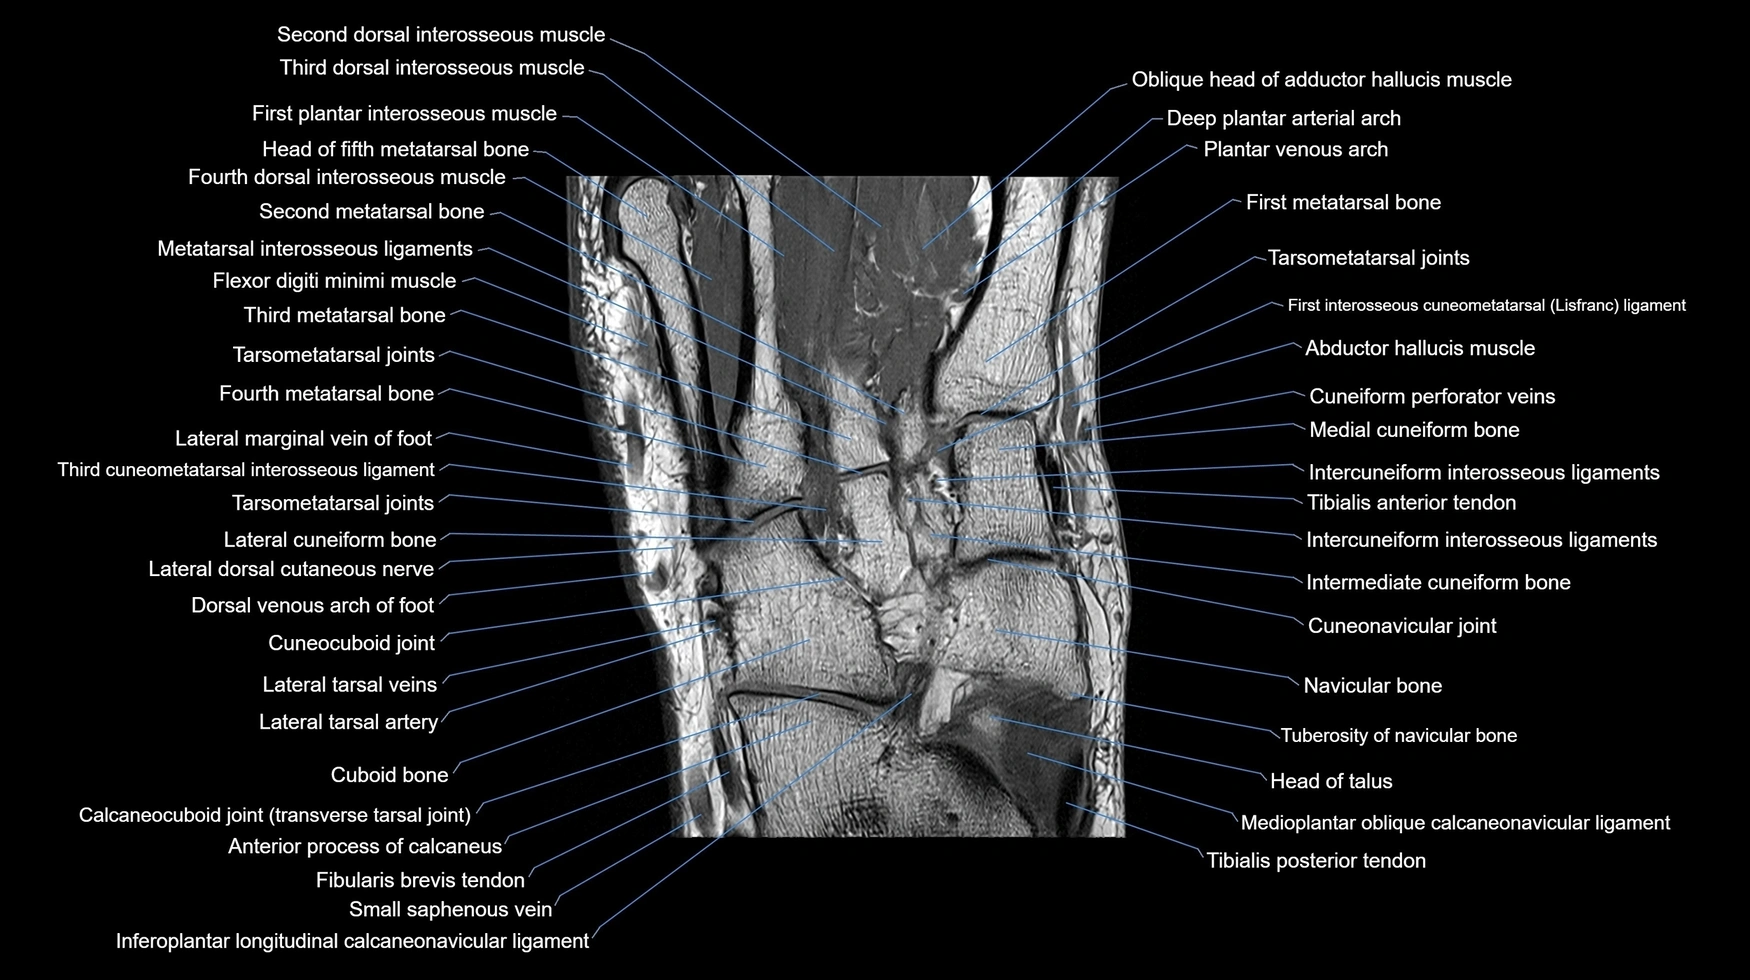

Experience the next generation of cross-sectional anatomy with our advanced 3T MRI, enhanced by AI-powered Deep Resolve reconstruction. Our ultra-high-resolution imaging (0.3–0.7 mm in-plane resolution) combined with ultra-small field-of-view techniques reveals fine anatomical detail with exceptional clarity, redefining anatomical visualization and education.

Explore an advanced library of ultra-high-resolution MRI anatomy, developed from hundreds of repeated scans of volunteers using cutting-edge 3T scanners, dedicated coils, and AI-powered enhancement. These images capture real anatomical detail, revealing even the smallest microstructures while preserving the authenticity of true clinical imaging without over-reliance on virtual labeling.

Learn MRI anatomy like never before—49 body parts, 144 planes

Crystal-clear, high-res images for effective large-screen teaching

All our cross-sectional images are meticulously hand-labeled by professionals with over 20 years of experience in cross-sectional imaging. This is the result of over six years of dedicated work, precision, and passion. Every image is individually checked and verified by senior consultant radiologists from major London NHS trusts, each with relevant subspecialty expertise—ensuring the highest level of accuracy and clinical relevance.